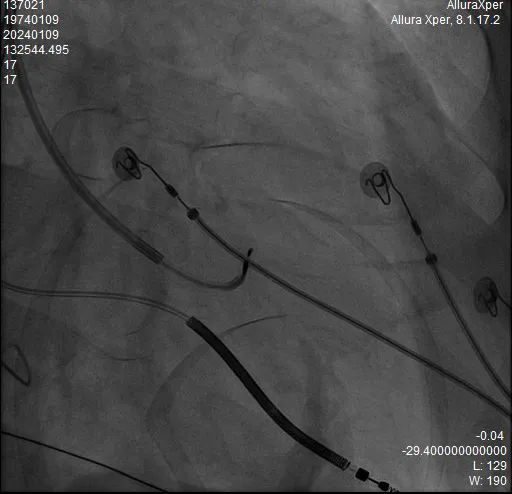

术中HIS电极影像

LBB影像位置

术中影像 HIS-HISD-消融靶点